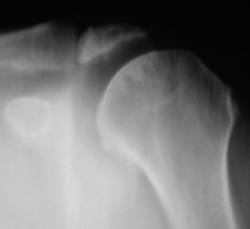

Иллюстрация 1 и 2. Рентгенограмма и фрагмент рентгенограммы с увеличением. В области головки плечевой кости определяются нерезко очерченные участки намечающегося остеопороза. Визуализируется нечеткость контура головки плечевой кости по латеральному контуру, в области большого бугорка. Определяется перестройка структуры костной ткани в области дистального отдела акромиального отростка лопатки. По верхнему краю определяется неровность и нечеткость контура. Решено произвести томографическое исследование.